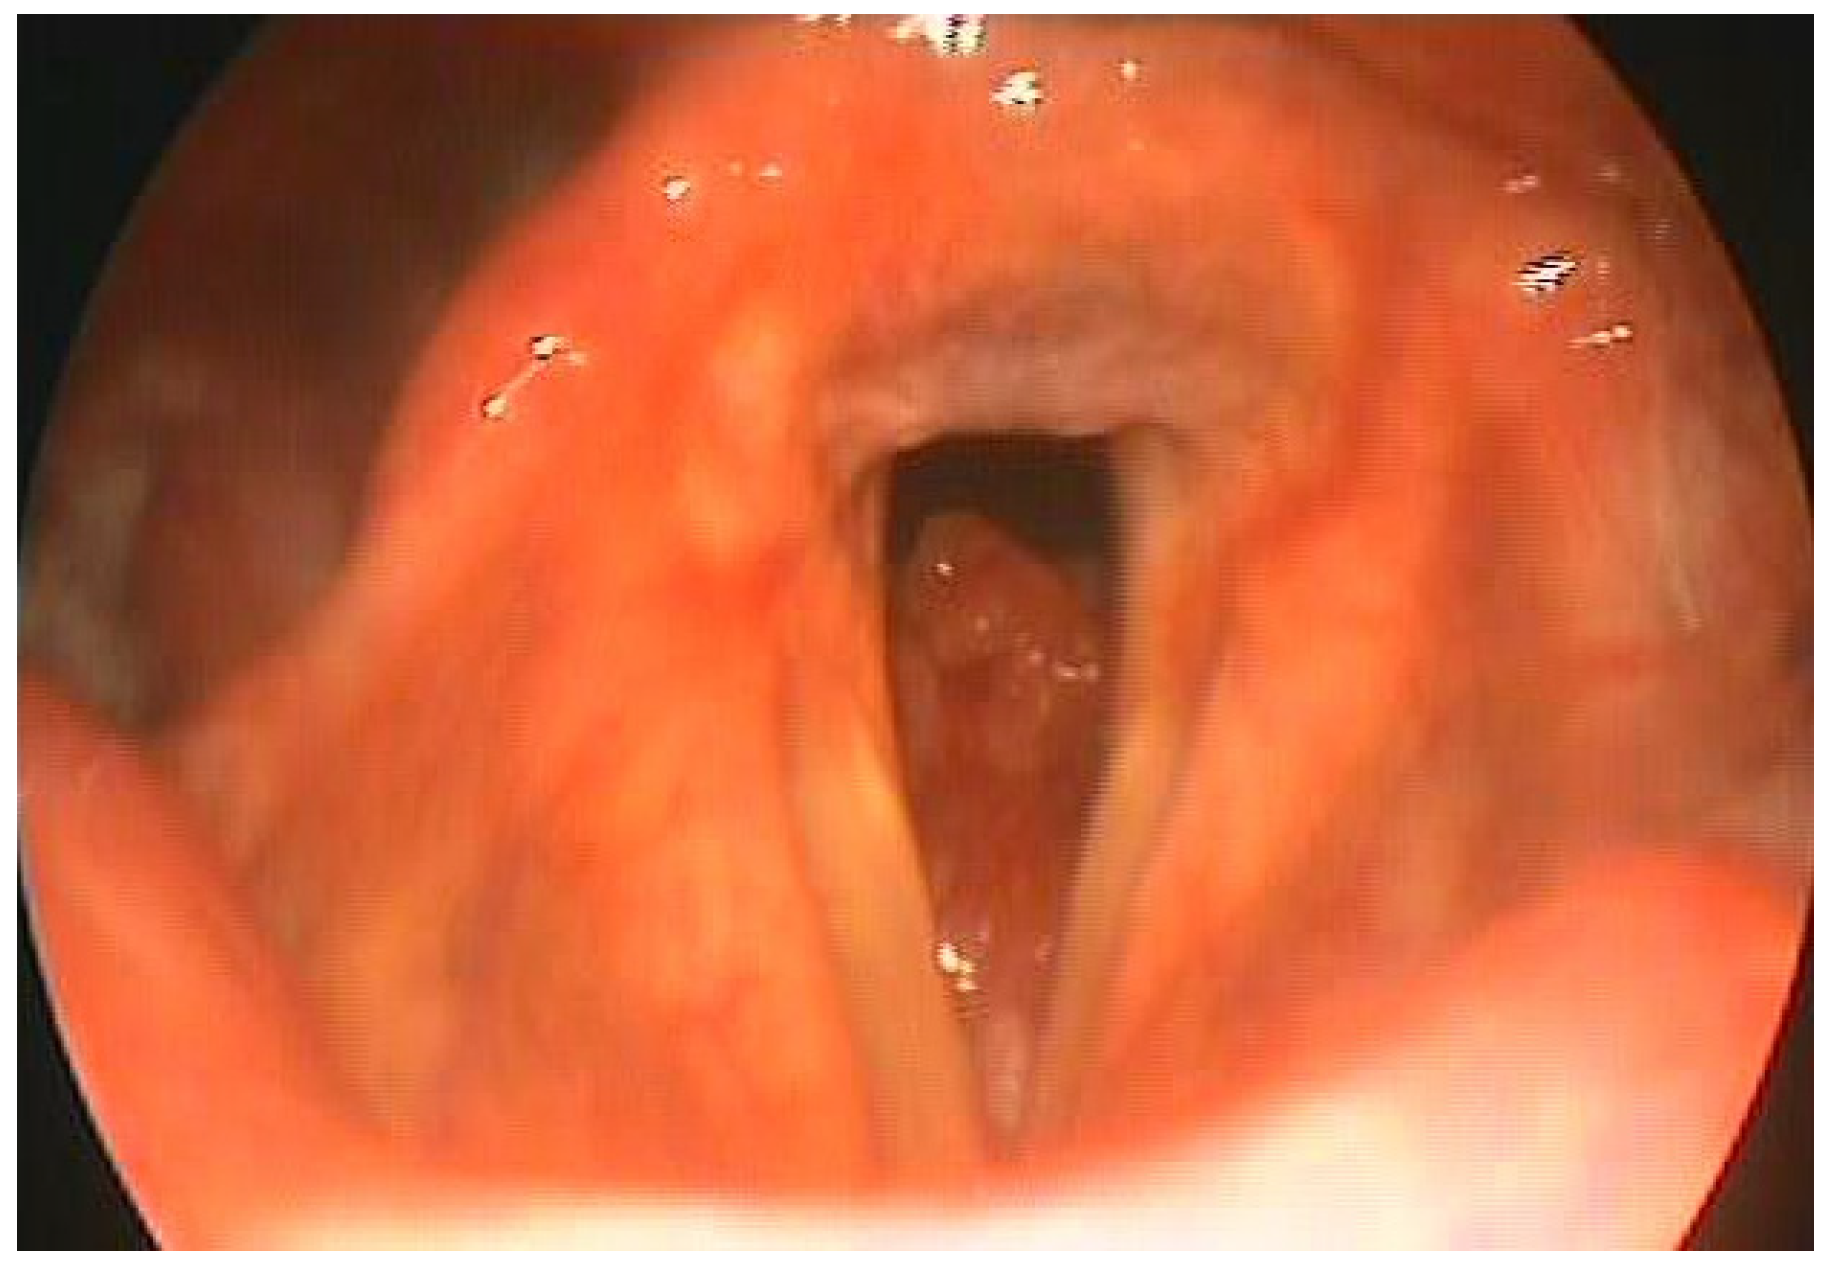

Currently, the patient continues to swim at an amateur competitive level (Figure 3).

Figure 3. Our patient during a race.